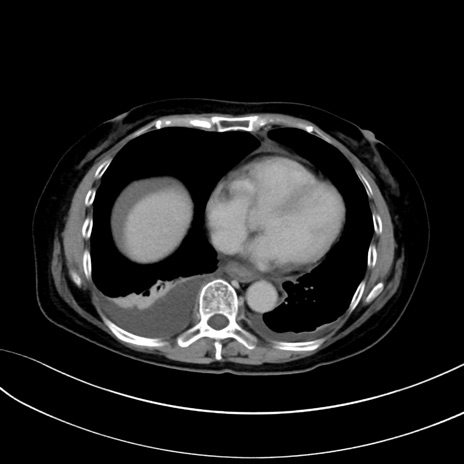

(冠状断像)1日半後